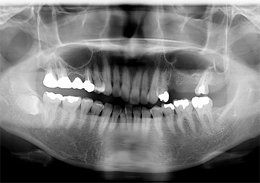

上顎のALL-ON-4(ノーベルクリニシャンを使用したフラップレス術式)

- 主訴

- 歯周病で歯がグラグラするので噛めない

- 治療内容

- 上顎に残存していた歯を抜歯。歯肉の治癒後にフラップレス手術にてインプラント埋入を行い、その場で準備してあった上顎上部構造を仮歯として、ねじ固定式で装着

- 治療費用

- 上顎ALL-ON-4:4,000,000円(税別)

- 治療期間

- 6ヶ月